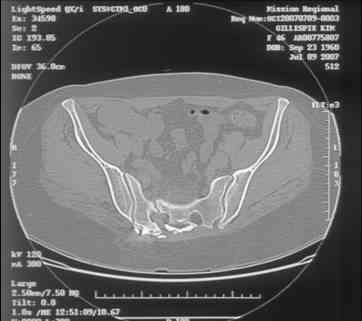

I can't see the axial CT images well enough to detail the potential sacral issues....can you magnify them?

Here is a magnified view. Sorry about the quality but the CT was scanned into our system.

Thank you...it might help to remove the disengaged and other iliosacral screws then insert longer lag screws into the upper sacral segment and if anatomically feasible into the second sacral segment as well.

You could do it percutaneously and even add an electrical stimulation device if that seems reasonable.

Delayed or non-union of a sacral fracture is a serious clinical condition that may include chronic pain, sitting discomfort, gait disturbances, neurological problems, and inability to work. It is also a difficult reconstruction problem.

Late correction of the deformity is technically more demanding than the primary treatment of acute pelvic injuries. Open reduction, internal fixation (ORIF), excision of scar tissue, and bone grafting

often in a multi-step approach are considered to be the treatment of choice in delayed unions of the pelvic ring. This procedure implies the risk of neurological and vascular injuries, infection, repeated failure of union, incomplete correction of the deformity, and incomplete pain relief as the most important complications. The lesion was successfully treated percutaneously in a single step procedure using CT navigation for drilling of the delayed union, autologous bone grafting, and screw fixation.